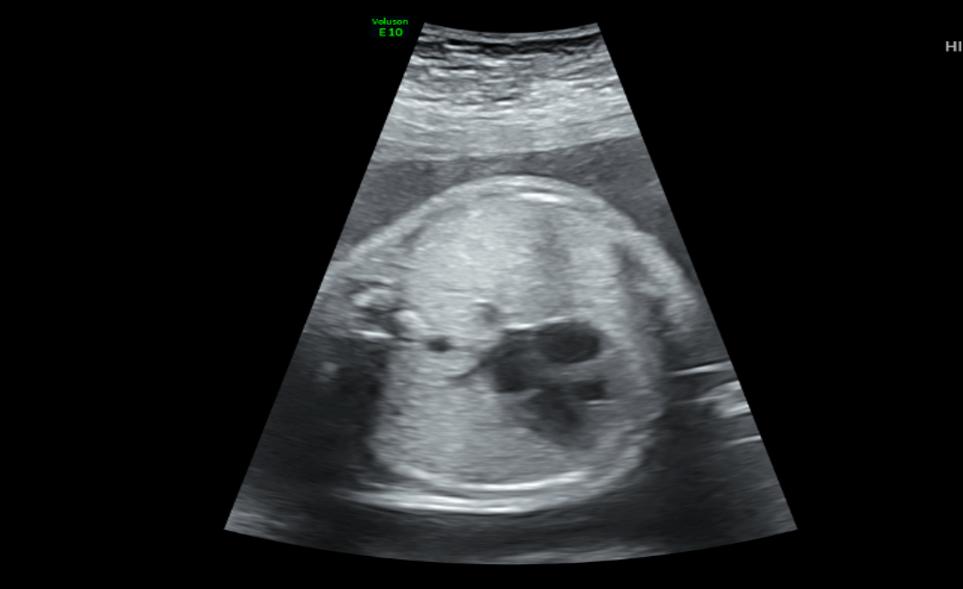

وأكد الدكتور هيثم بدر رئيس قسم طب النساء والولادة، أن الأم البالغة من العمر 19 عاماً كانت قد راجعت عيادات متابعة الحمل بالمستشفى وتبين أثناء الفحص الإشعاعي وجود تشوه خلقي في المجرى التنفسي للجنين.

وقال: ” تم عرض الحالة على طاقم من الأطباء المختصين في عيادة الحمل عالي الخطورة بقيادة د. نوف العجاجي و د. الهام المرداوي استشاريات طب النساء والولادة، إذ تم وضع الخطة العلاجية الملائمة للأم والجنين وتحديد موعد الجراحة القيصرية بناءً على عمر الجنين.